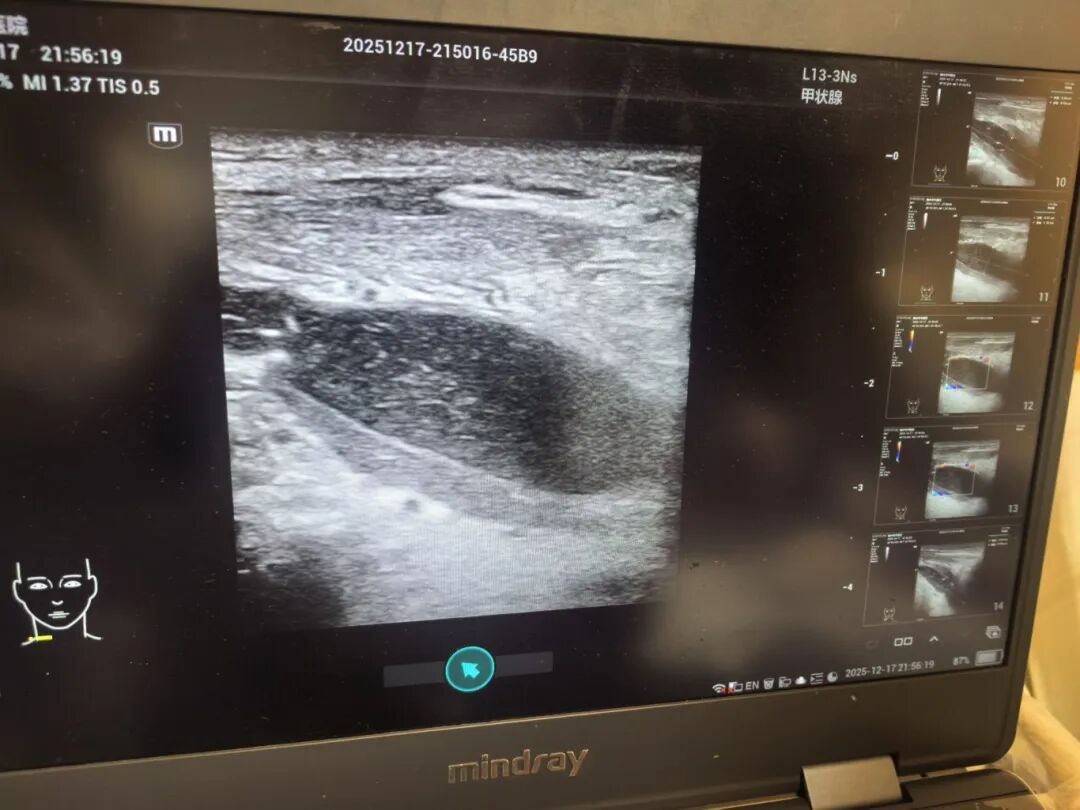

在医院急诊科,医生在B超引导下为郑先生行颈部穿刺术后,结果令医生捏了一把汗——郑先生颈部存在巨大脓肿,感染灶紧邻颈部大血管,且已对气管形成压迫,随时存在窒息风险,必须立即手术引流。